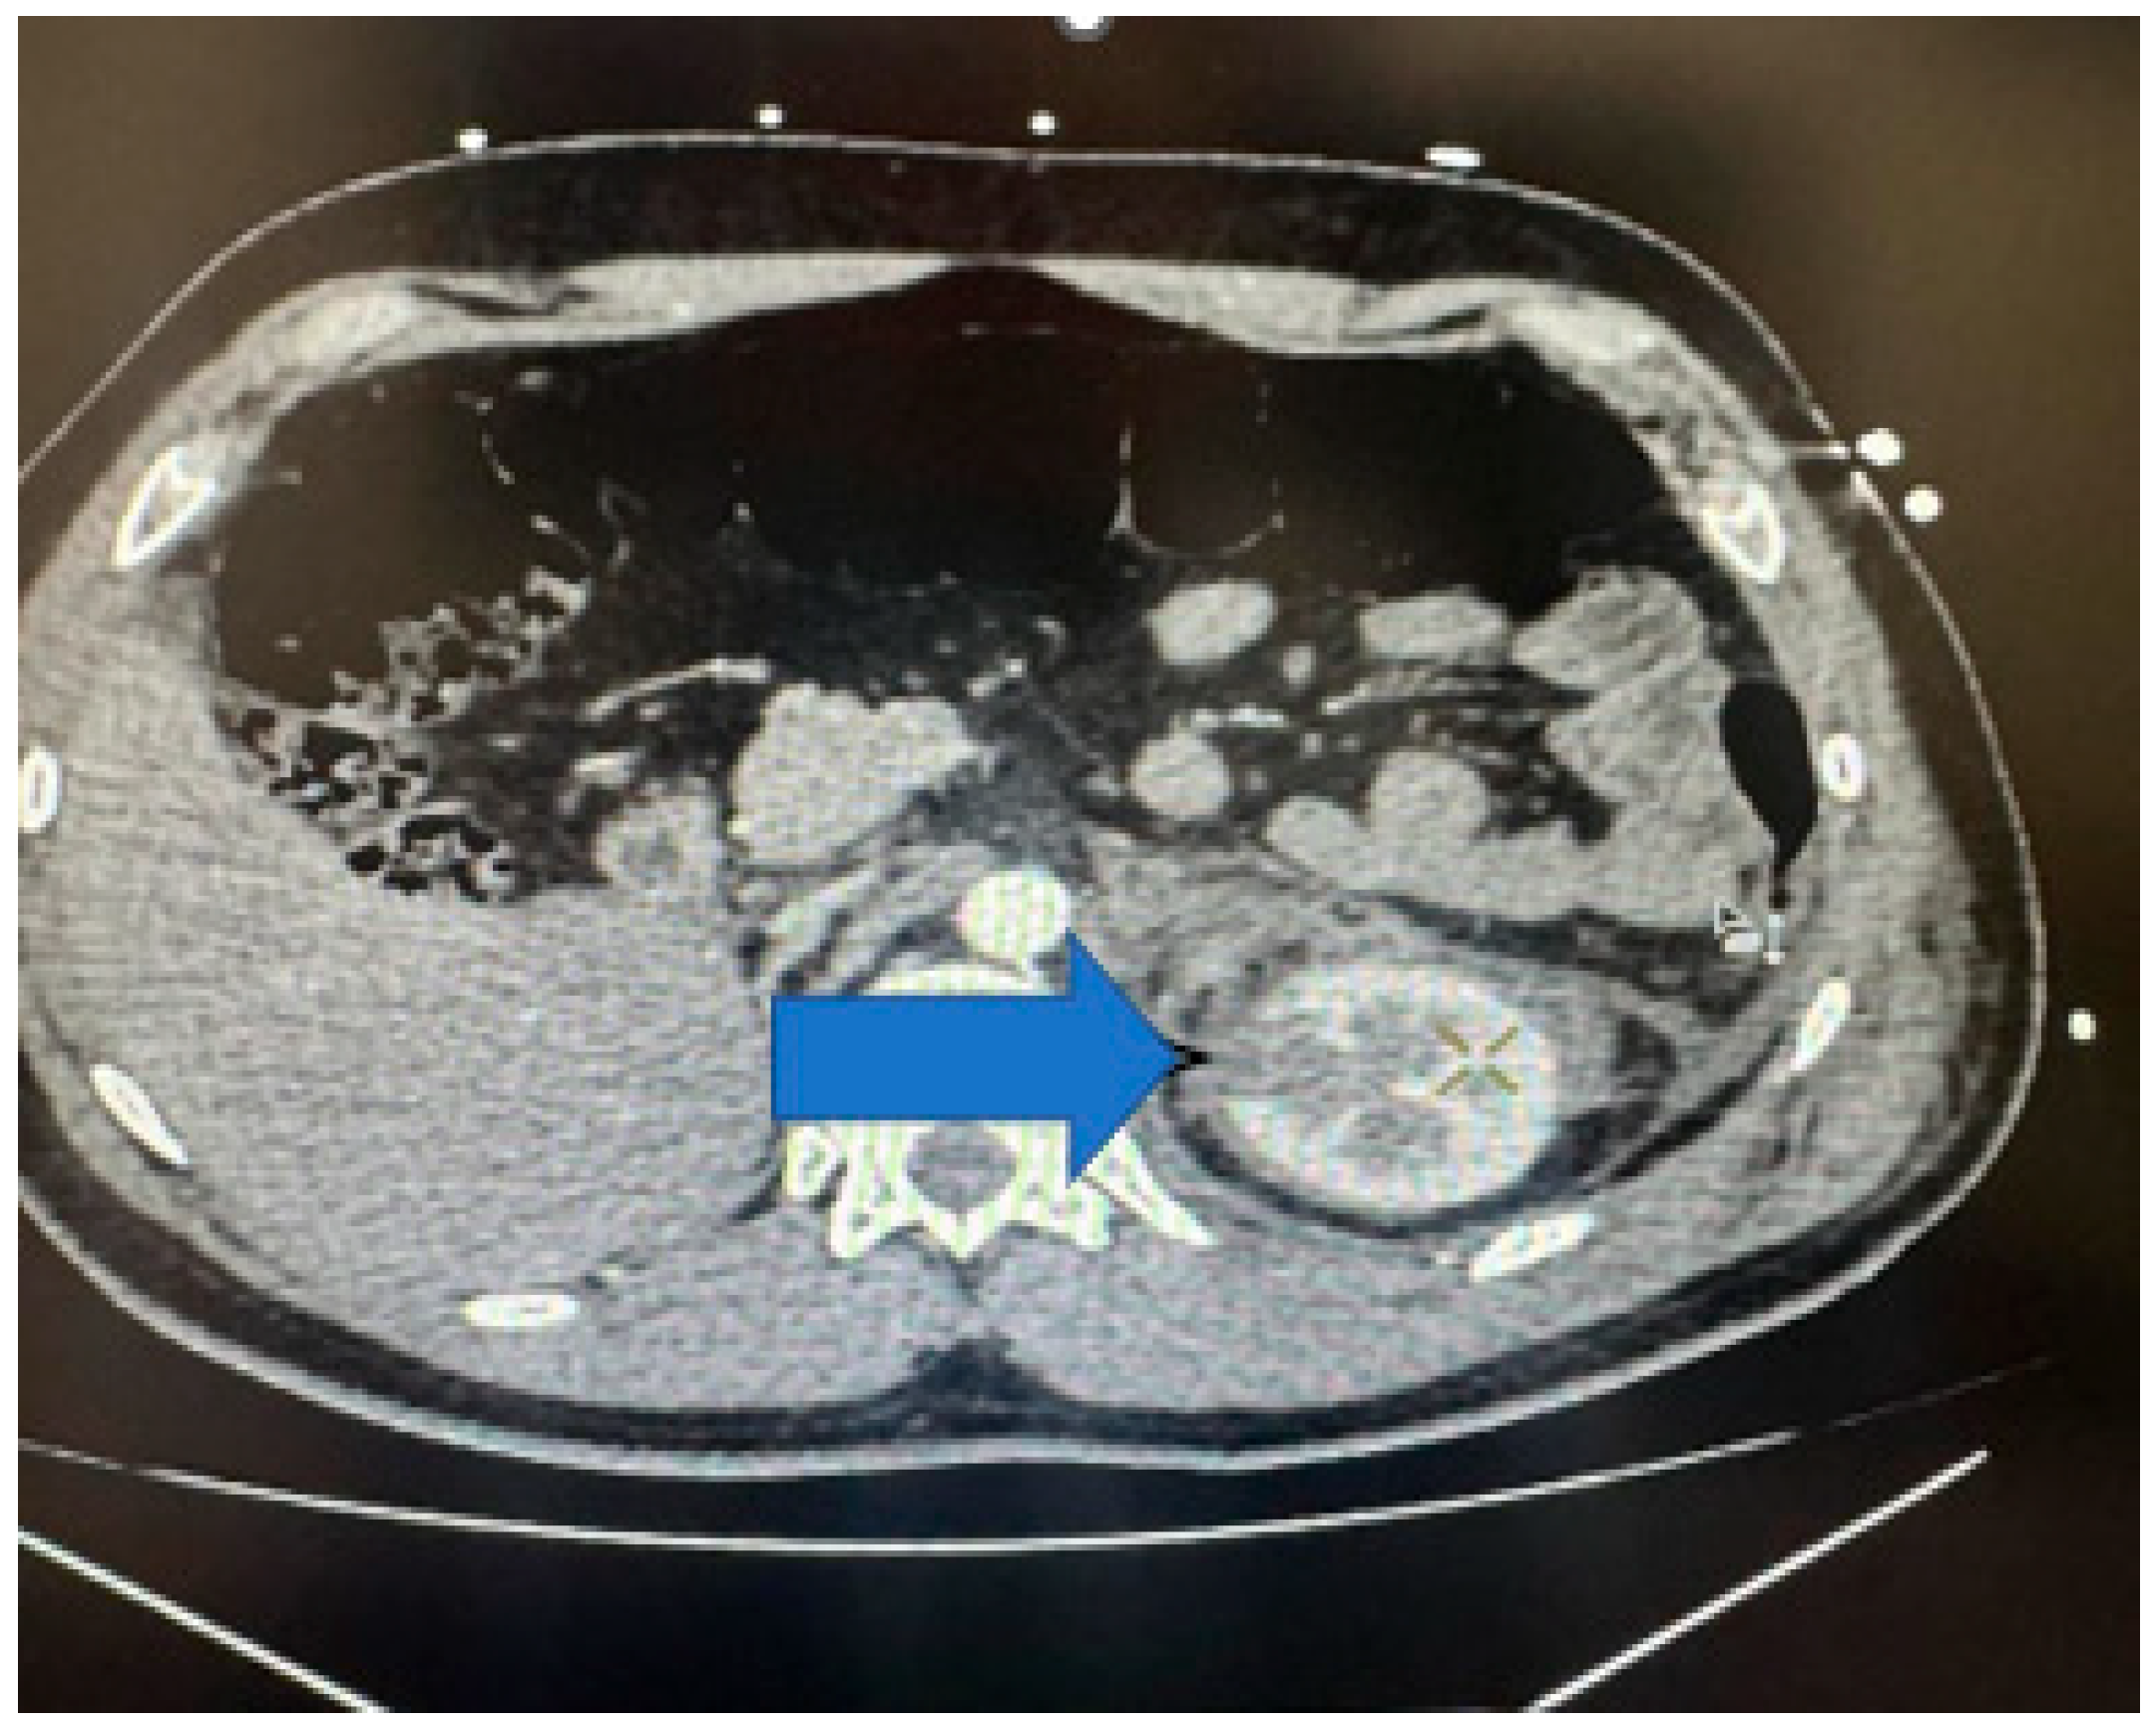

The distribution of the renal injuries, according to AAST classification (Figure 5), in this study is the following: grade 1 (Figure 6) (26.97%), grade 2 (Figure 7) (34.83%), grade 3 (Figure 8) (19.10%), grade 4 (Figure 9) (10.11%), and grade 5 (Figure 10 and Figure 11) (8.99%).

Figure 10. Contrast-enhanced CT scan showing left-kidney grade 5 injury—avulsion of renal hilum with large hematoma, axial section.